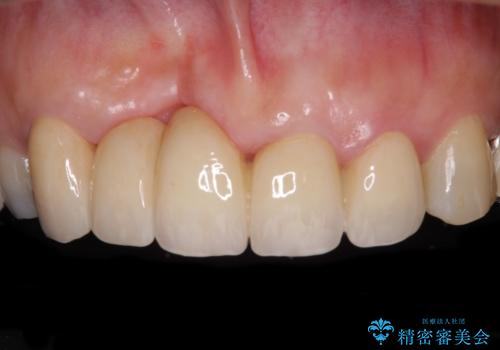

歯周病改善のための総合歯科治療